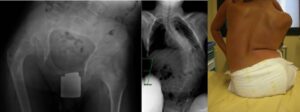

In milder cases of initial hip joint dysfunction, conservative treatments are often considered (physiotherapy, Botox injections, orthopedic braces that keep the limbs abducted, i.e., spread apart, to better center the hips). Unfortunately, most of these treatments have never been proven to be truly effective, and the outcome is often uncertain.

- the severity of the dislocation (evaluating specific radiographic parameters)

- the clinical picture (hip mobility, symptoms, association with scoliosis, pelvic obliquity, windblow, etc.)